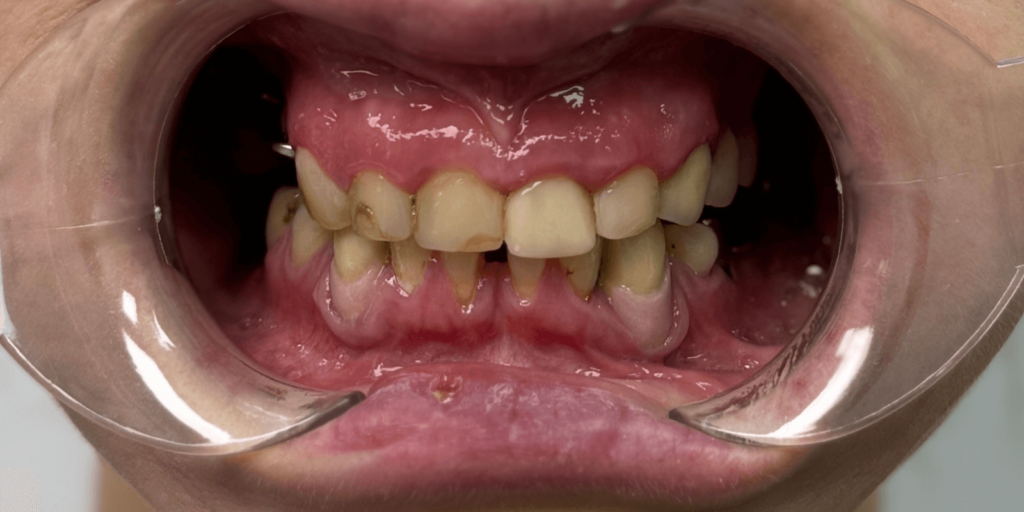

В нашу клинику обратилась женщина с многолетней усталостью в глазах. Она не могла нормально пережевывать пищу, стеснялась своей улыбки и постоянно подсознательно прятала лицо во время разговора. Ее беспокоили не только эстетические проблемы — отсутствуют зубы, старые мостовидные протезы, потемневшие пломбы, — но и функциональный дискомфорт, каждый день напоминавший о себе. Во время первичного осмотра (визуально) врач увидел:

- На верхней челюсти: 5 фронтальных зубов покрытых реставрационными пломбами, в области зубов 2.3-2.5 установлен металлокерамический мостовидный протез, 5 зубов отсутствуют. Установлен мостовидный протез в области зубов 1.4, 1.5, 1.6 с опорой на зубы 1.5 и 1.6. Зуб 1.7 покрыт металлокерамической коронкой.

- На нижней челюсти отсутствуют 5 зубов, передние зубы с большой тремой между ними, зубы 4.3 и 3.3 покрыты коронками из металлокерамики, на зубах 3.4, 3.5, 3.8 установлены большие корневые вкладки.